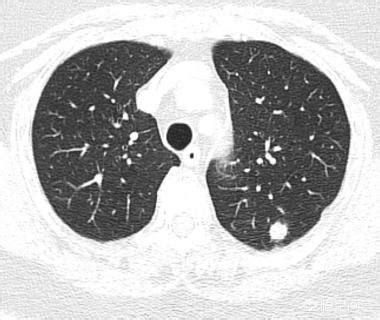

矢印は結節を指しているが、2016年3月に発見されたときは約0.5cmと非常に小さかったが、今では定期検診でこのように非常に多くの結節が見つかっている。画像で良性か悪性かを判断する方法はなく、検討するという選択肢しかなく、検討と経過観察も最良の手段である。